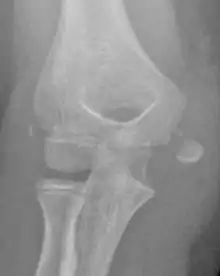

The diagnosis is confirmed with X-rays and occasionally with a CT scan.

In all injuries to the medial epicondyle, radiographs (x-rays) are imperative. Computed tomography scans are occasionally useful in evaluating the degree of fracture displacement or the involvement of the joint surface.

Displaced Fracture

Studies generally use the x-ray appearance of the arm to determine how displaced a fracture is. The definition of ‘displaced fractures' are variable, with anything from 2mm to more than 15mm;[4] however x-rays on which this assessment is made are known to be hugely misleading with fractures showing little displacement having >10mm displacement using CT scans.[5][6] The practical approach is therefore to assume that any fracture that has any degree of displacement on x-rays is ‘displaced’.